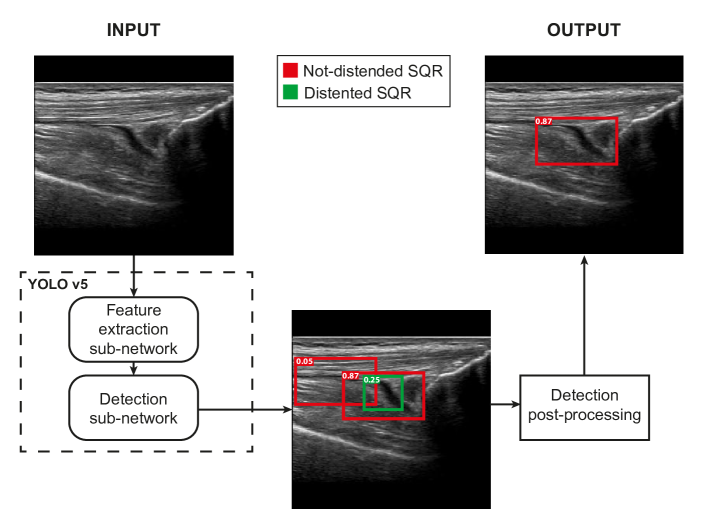

Figure 3 depicts the network architecture of the Detection approach.

Refer to caption

Figure 3: Overall architecture of the Detection approach

Each input US image is processed by the YoloV5 [46] object detector that returns a set of candidate SQRs, each characterized by a confidence value, a bounding box and the label (Distended or Non-distended). Since in the considered domain the input image actually contains exactly one SQR, the Detection Post-processing module selects the prediction with highest confidence and outputs its bounding box and its label.

We train the network to recognize two classes of objects: Distended SQRs and Non-distended SQRs. Since the amount of labeled images in in this domain is generally scarce, it is difficult to collect a sufficiently large dataset to fully train a robust detection network. Therefore, we adopt a transfer learning approach [47] to initialize the network’s weights. Specifically, we use the pre-trained weights publicly available for the YoloV5 network trained on the MS COCO dataset [48]. Finally, the network is fine-tuned on the actual dataset containing the labeled US images.

YoloV5 is a single stage detector designed to detect different objects in a image and directly assign them the corresponding class. YoloV5 is an optimized version of the YoloV4 framework [49], that has been widely used in the literature for object detection tasks. Specifically, among the five models available in YoloV5, we use the large model, which was empirically selected. YoloV5 is internally divided into a feature extraction sub-network and a detection sub-network. It also adopts a specific loss function and an early stop criterion. These four concepts are briefly described in the following.